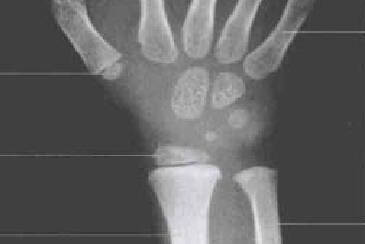

腕骨骨化中心出现的时间

头钩三角月

舟大小豌豆